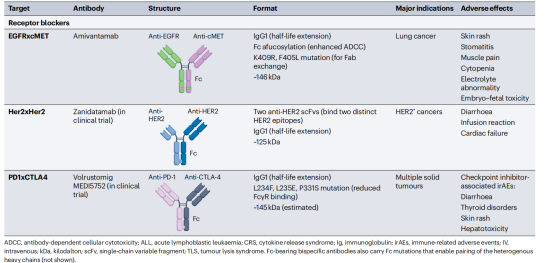

双特异性抗体也被设计用于结合目标癌细胞上的两种不同抗原或表位,而不涉及效应T细胞。它们的抗癌作用是通过阻断两种增殖信号通路介导的,从而最大限度地发挥抗肿瘤活性。除了它们的受体阻断活性外,这些双特异性抗体也可以被设计成含有一个功能性的IgG1Fc结构域,使它们能够通过非T细胞免疫效应途径(如ADCC、ADCP和CDC)杀死癌细胞。Amivantamab是第一个靶向癌细胞表达的EGFR和MET的受体阻断双特异性抗体被批注用于治疗非小细胞肺癌,Amivantamab的IgG1Fc结构域被设计成低聚焦水平,从而增强FcγRIIIa结合和NK细胞介导的ADCC。TCE双特异性抗体会引起细胞因子释放综合征(CRS)和神经毒性,受体阻断双特异性抗体不能激活T细胞,一般不会诱导CRS和神经毒素。